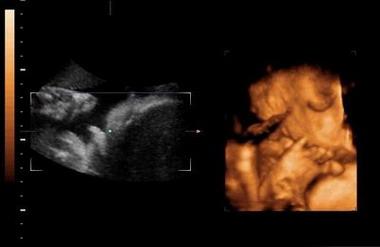

四维超声是一种比较先进的检查方式,也是实时的动态三维超声,一般来说通过四维超声来辨别宝宝性别是比较准确的,四维单子上出现了四个字的就是怀了男宝,更多关于生男生女的相关内容尽在孕宝网,欢迎关注。

四:通过四维彩超图看清胎儿性别,在六个月以后照四维彩超,只要宝宝的姿势是正面不是给个背影什么的,是男是女一看就知道。不过因为国家明文规定不能查胎儿性别,所以医生不会把能明显看出性别的一面照给妈妈看。